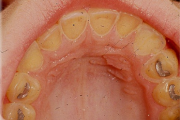

Laste ja noorukite söömishäired. Anorexia nervosa, Bulimia nervosa